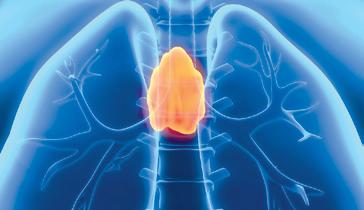

вий мозок, тимус) і

належать гіпофіз (1), епіфіз (2), щитоподібна (3), прищитоподібні (4), вилочкова (5), надниркові залози (6); • залози змішаної секреції (мезокринні залози) — це залози, які

Організм людини, як і інших живих істот, має захисні механізми, що захищають від вірусів, хвороботворних бактерій, паразитичних грибів і тварин, шкідливих речовин, токсинів та канцерогенів, звільняє від перероджених власних клітин. Імунна регуляція забезпечується багатьма системами організму, наприклад, шкіра, дихальна система, травна система, ендокринна система, система крові.